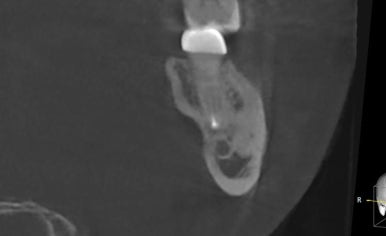

이번 환자분은

왼쪽 아래 어금니 (#37)에

👉 강한 통증을 느끼고 내원하셨습니다.

검사 결과,

✔ 이미 신경치료 + 크라운 치료가 되어 있었고

✔ 치아 뿌리 끝에 큰 염증이 형성된 상태였습니다

👉 이런 경우는 흔히

**“재발성 치근단 염증”**이라고 합니다.